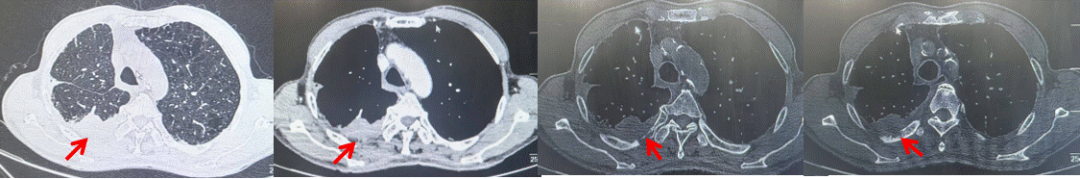

2024.09.12复查胸部CT示左侧胸膜结节,大者约为27mmx13mm,考虑转移可能性大,纵隔淋巴结增大,恶性?(如图6)。患者行胸膜穿刺活检取病理,结果示(胸膜)结合免疫组化,支持鳞状细胞癌,PD-L1(克隆号28-8)TPS约20%。分期为rT0N2bM1a IVA期,DFS为10个月。2024.09.24起行替雷利珠单抗联合紫杉醇+卡铂方案治疗4周期,复查胸CT评效SD(如图7)。后患者因脑梗塞停止治疗,于综合医院就诊,后未返院复查及治疗。

图5:患者手术前(2023.11)胸部CT肺窗及纵隔窗

图6:患者胸膜及纵隔转移(2024.09)胸部CT肺窗及纵隔窗

图7:替雷利珠单抗联合白蛋白紫杉醇+卡铂治疗4周期后(2024.12)胸部CT肺窗及纵隔窗